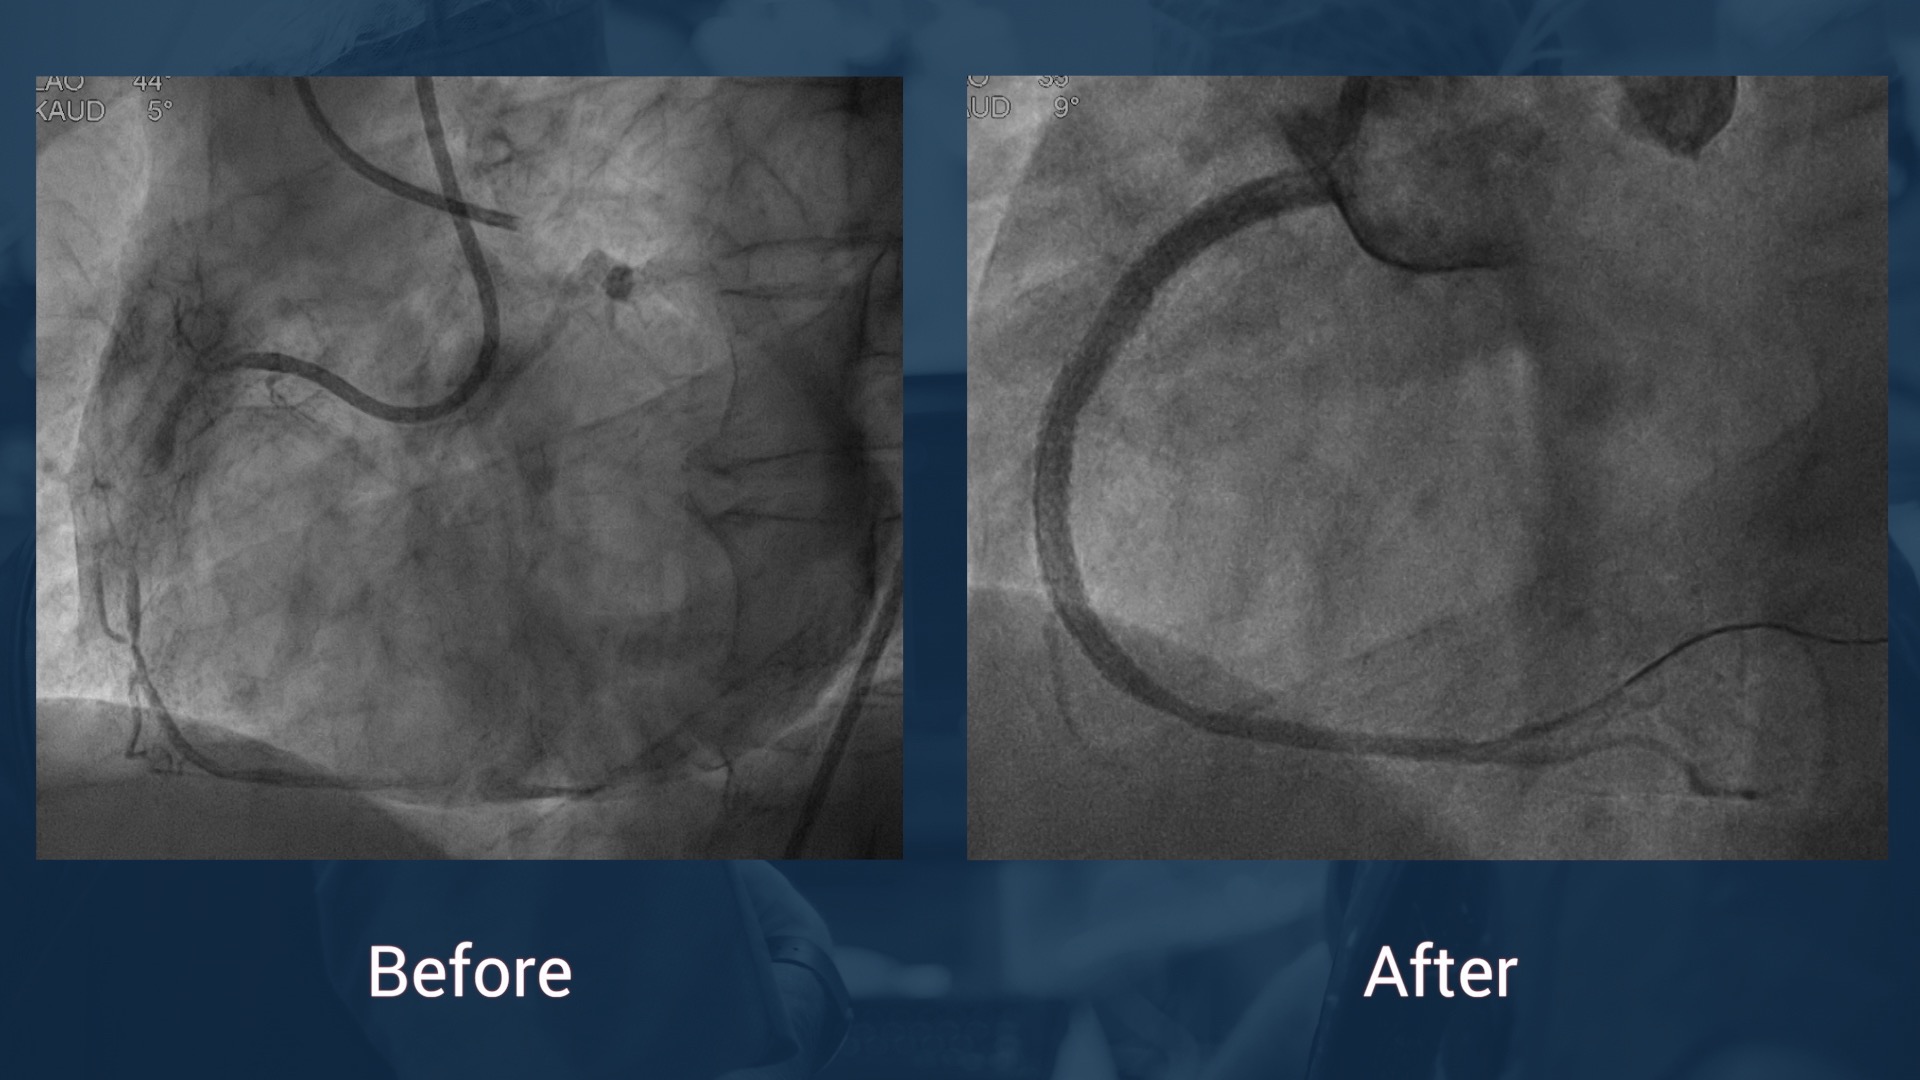

7/97 PCI of RCA with BMS

2013 CTO PCI of the RCA with 4 DES (Xience) for angina

CAG 14.7.17: LAD without stenosis, CX without stenosis, in-stent reocclusion of the RCA

J-CTO score: 1